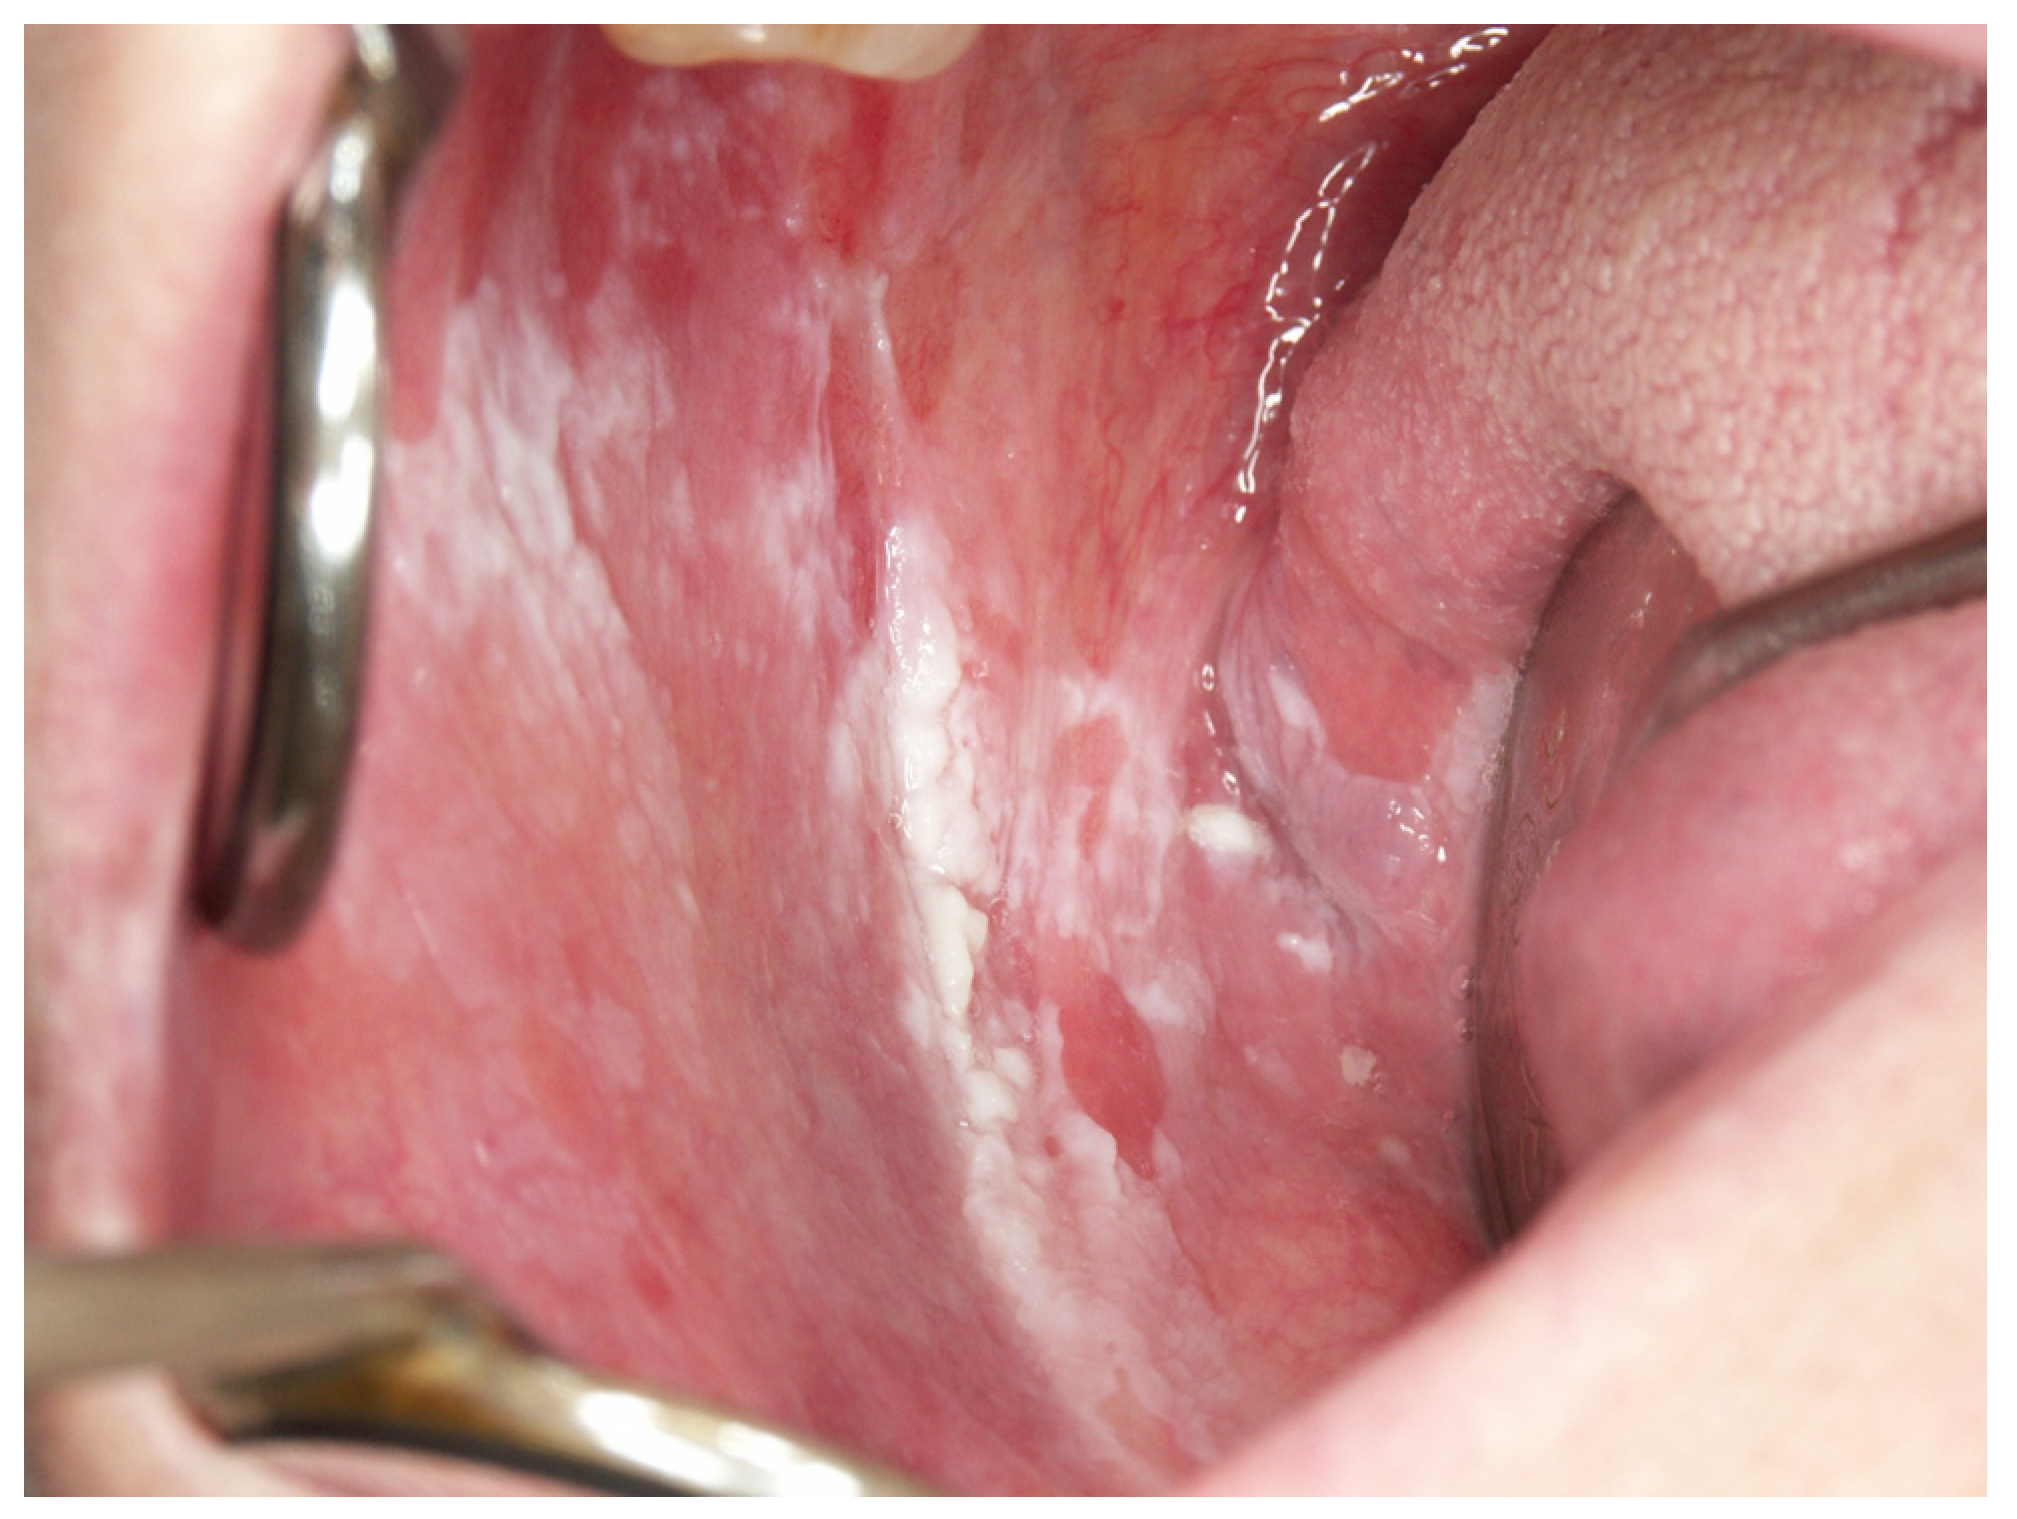

Appendix A. Clinical Presentation of OPMD